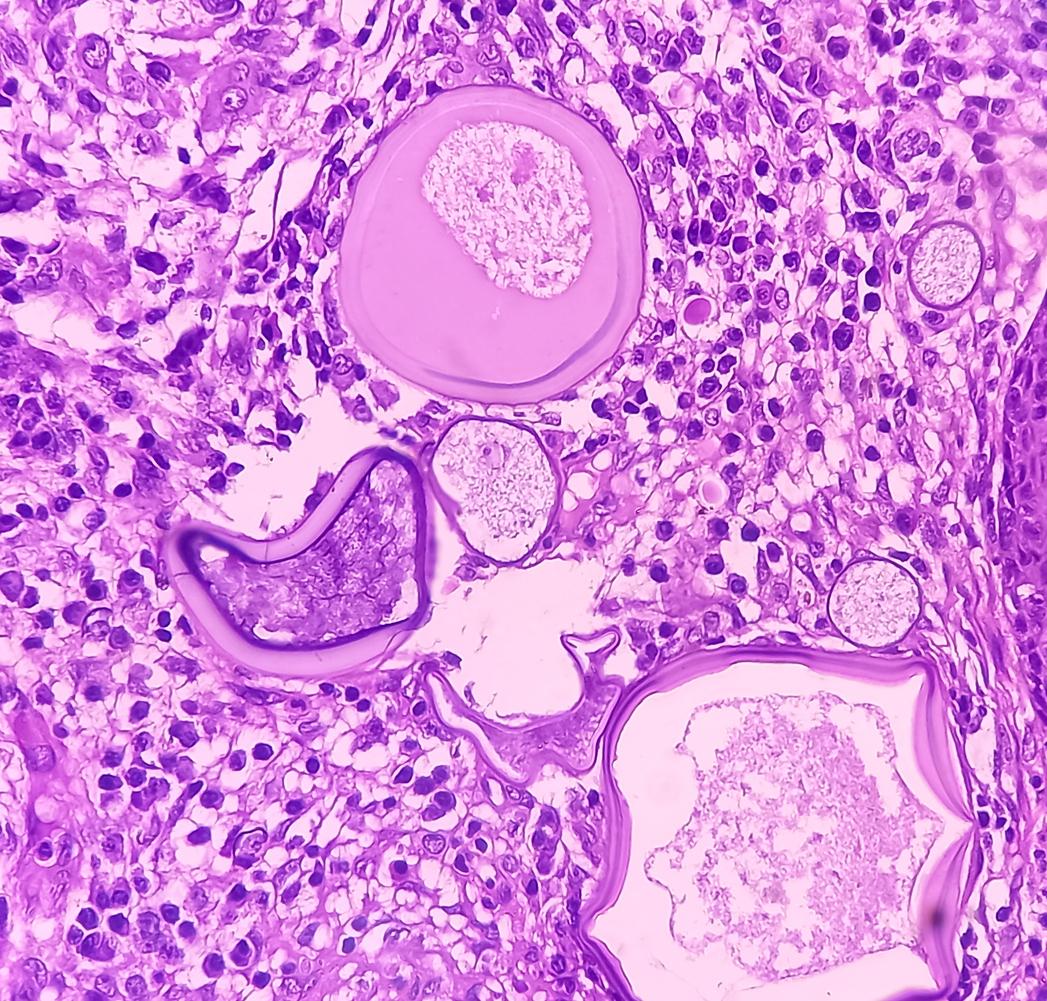

Le patient a été pris en charge par des chirurgiens du All India Institute of Medical Sciences. La tumeur a été retirée lors d’une intervention chirurgicale. Elle mesurait quinze centimètres (cm) de diamètre et s'accrochait à un lambeau de tissu oculaire de quinze cm de long, mais elle n’était pas cancéreuse. D’après leurs conclusions, publiées dans le British Medical Journal, l’homme souffrait d’un angiofibrome associé à une rhinosporidiose, une infection parasitaire.

Pour l’équipe médicale, la tumeur est survenue en raison de la présence du parasite. Le corps a réagi à cette infection en enflammant les tissus environnants. Les médecins ne savent cependant pas depuis combien de temps le patient avait ce parasite au sein de son organisme ou comment il l’avait attrapé.